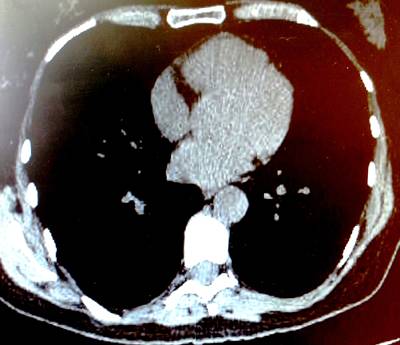

- Radiografía de tórax anormal (nódulos, infiltrados o cavidades)